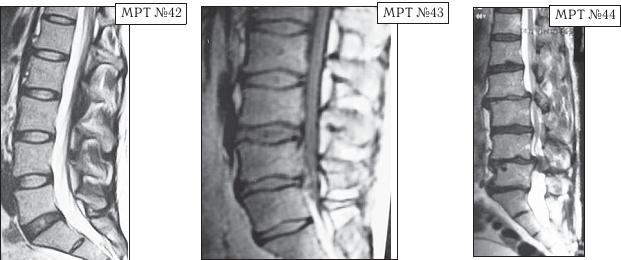

Для лучшего понимания того, что именно может собой представлять стеноз позвоночного канала, обратимся к визуальному сравнению МРТ снимков. Напомню, что нормальный сагиттальный размер позвоночного канала в поясничном отделе позвоночника должен быть не менее 15 мм; от 15 мм до 11 мм — относительный стеноз; менее 10 мм — абсолютный стеноз.

МРТ № 42 — снимок приведён в качестве «нормы» для дальнейшего сравнения снимков поясничного отдела позвоночника.

На МРТ № 43 наблюдается поясничный отдел позвоночника с врождённым (первого типа) абсолютным стенозом позвоночного канала.

На МРТ № 44 наблюдается поясничный отдел позвоночника с приобретённым (второго типа) абсолютным стенозом позвоночного канала.

Если Вы внимательно посмотрите на МРТ № 44, то увидите, как «обычный» дегенеративно-дистрофический процесс может привести к развитию абсолютного стеноза (второго типа) с полным сдавлением спинномозгового канала на уровне LII—LIII и LIV-LV, костными разрастаниями и ретролистезом (смещение позвонка кзади) тела LV поясничного позвонка. Естественно, что у данного пациента серьёзные проблемы с нижними конечностями («параплегия» — паралич обеих ног) и нарушения функции тазовых органов. Единственное, что может ещё помочь больному в этом случае, это хирургическая операция — декомпрессия позвоночного канала. Кстати говоря, первая подобная операция, так называемая декомпрессивная ламинэктомия на поясничном отделе позвоночника, была выполнена в 1900 г. пациенту с подобными нарушениями. И опять-таки мы сталкиваемся с тем, что лучше не допускать развитие заболевания, чтобы потом не оказалось слишком поздно что-либо исправить нехирургическим путём. Есть хорошее выражение: «Тот не мудр, кто из науки себе пользы не извлекает».